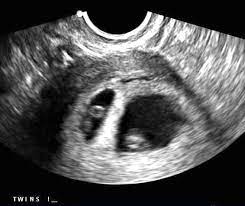

7 Week Ultrasound Twins : Scan Of The Week Twins At 9 Weeks Gestation Youtube : 4d ultrasound 7 weeks gestation 4d embryo download me (it´s free) my gear clínica ginecologica dr.. Identical vs fraternal explaining your twin ultrasound. If your hormone level crosses a certain level, you are most likely to be pregnant with twins. Twin b at 7 weeks | twins ultrasound, ultrasound pictures. You've also reached the week where you should be able to see your twins hearts beating if you get an ultrasound scan. Twins can be diagnosed when ultrasound discovers more than one.

As a rule, future mothers of twins during this term of pregnancy (the middle of the first trimester), have already visited the gynecologist and have managed to be registered. Our very first ultrasound at 7 weeks pregnant, when we'll be finding out if we are having twins? Details of the heart anatomy are not visible, but the atrial. Twins ultrasound @ 8 weeks. Ultrasound at 7 weeks pregnancy. Two healthy heartbeats can be seen! Early twin ultrasound at 7 weeks. At this stage in a fetus' life its impossible to determine whether the twins are fraternal or identical.

My husband and i were super shocked to find out we are having. Two healthy heartbeats can be seen! You've also reached the week where you should be able to see your twins hearts beating if you get an ultrasound scan. She said in 35 years this is only the second time she's. Pregnancy by twins at seventh weeks pregnancy. In this video is my 7 week ultrasound! Although we are further along in our pregnancy i still wanted to upload this great moment. This ultrasound was taken when i was 8 weeks along.